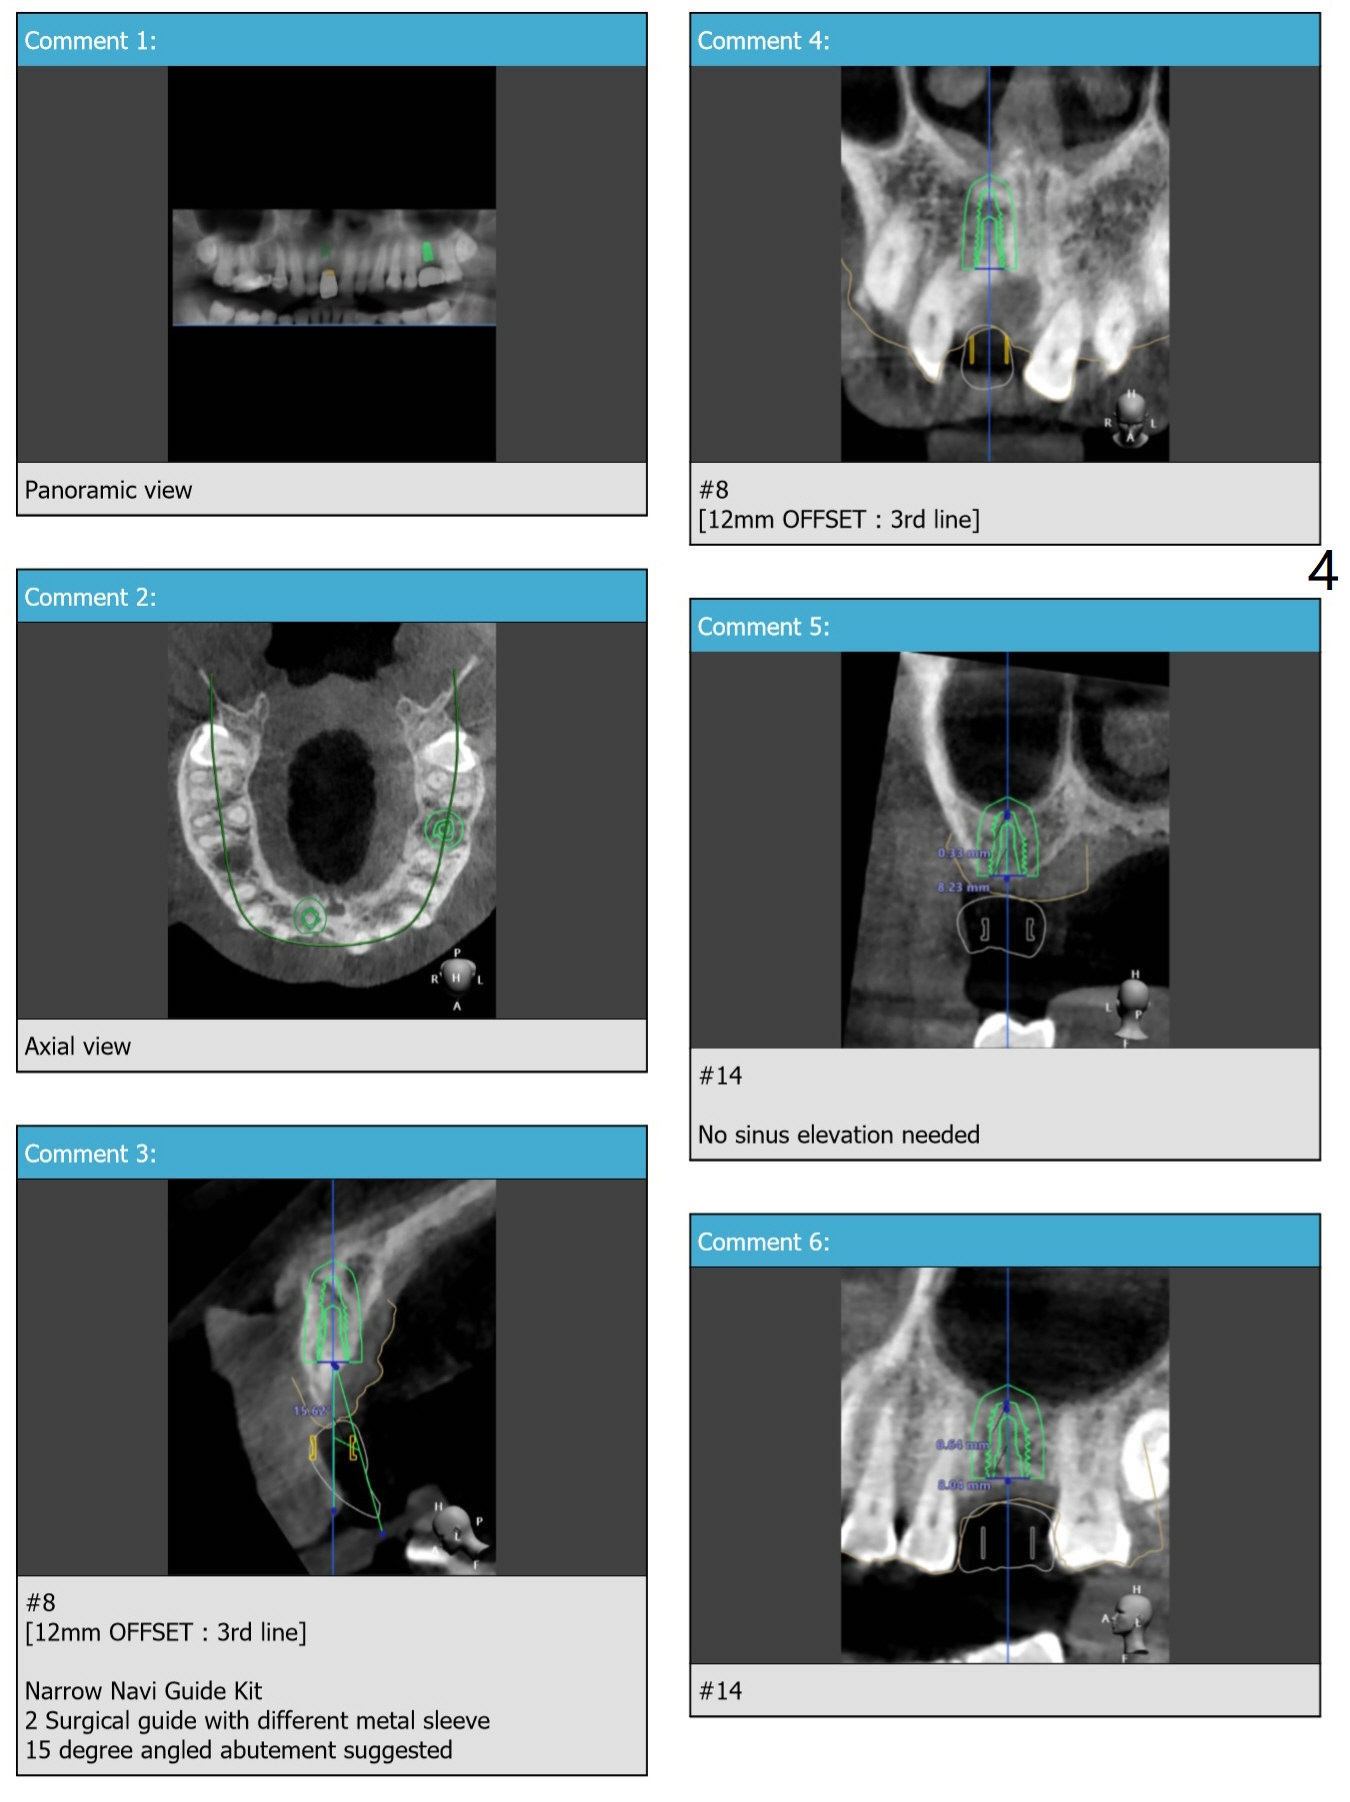

Narrow Implant with Angled Abutment

Return to Upper Incisor Molar Immediate Implant, Trajectory Protect Graft